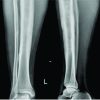

A 72-year-old female patient presented to our emergency department with an inability to walk following a fall at home, resulting in a displaced fracture of the right femur. Physical examination and X-ray imaging confirmed a diagnosis of an Arbeitsgemeinschaft für Osteosynthesefragen/Orthopedic Trauma Association type 31; A2.2 [8]. Right intertrochanteric femur fracture and surgical intervention were recommended (Fig. 1a). The patient had a known history of hypertension. A pre-operative routine single dose of anticoagulant regimen, including 0.4 mg of low molecular weight heparin, was initiated.

Preoperative laboratory findings showed hemoglobin level of 9.3 g/dL, hematocrit (Hct) of 30.3% and an international normalized ratio of 1.16. On the 3rd day of hospitalization, the patient underwent surgery, which was performed using a traction table. A 3–5 cm incision was made approximately 4 cm proximal to the greater trochanter. After blunt dissection of the abductors, a guidewire was inserted from the major trochanter. Only the nail entrance at the greater trochanter was reamed using a 14 mm reamer. An 11/220 mm diameter nail (PROFIN®, TST Ind., Istanbul, Turkey) was introduced over the guide wire. Proximal fixation was achieved with 8.5 × 100 and 8.5 × 95 mm two lag screws, and distal fixation with a 5.0 × 36 mm screw (Fig. 1b). After achieving hemostasis and conducting fluoroscopy checks, the procedure concluded. Postoperative laboratory assessments at 12 h post-operation revealed a hemoglobin level of 5.6 g/dL and Hct of 18.1%. Due to the low hemoglobin level, two units of blood were transfused. Subsequent blood tests indicated a post-transfusion hemoglobin level of 8.9 g/dL and Hct of 26.9%. On the 1st postoperative day, hemoglobin measured 8.8 g/dL and Hct was 26.5 g/dL. To address a further decline in hemoglobin level (8.2 g/dL) and Hct (25.6%) on the same day in the evening, an additional unit of blood was transfused. Subsequent hemoglobin and Hct levels during follow-up were 9.6 g/dL and 26.3%, respectively. Minimal discharge was observed during wound dressings on the 1st post-operative day, and no discharge occurred on the 2nd and 3rd days. The patient was instructed to perform physiotherapy exercises. With a clean wound and normal blood parameters, the patient was discharged with a prescription that included 0.4 mg of low molecular weight heparin, oral ferritin, paracetamol, and a proton pump inhibitor.